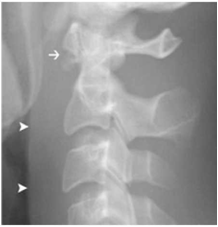

מהערכה רדיולוגית נדרשת: אבחנה, סווג הנזק וקביעת היות הנזק יציב או לא. ב-70% מהחולים הנזק נראה בצילומי עמוד שדרה (תצלום 7.16) ואינם דורשים המשך ברור. יש לזכור ש-30% מהנזקים לעמוד השדרה אינם נראים בצילומי רנטגן רגילים ודורשים CT או MRI (תצלום 8.16). חולים עם נזקים רציניים לעמוד השדרה או חולים מורכבים, יעברו CT ספירלי כאמצעי אבחון ראשוני דחוף. בחשד לפגיעה ברקמות רכות או בחוט השדרה בדיקת הבחירה הדחופה היא MRI של עמוד השדרה. המכניזם של השברים והגדרתם כיציבים או לא מופיעה בטבלה 6.16.